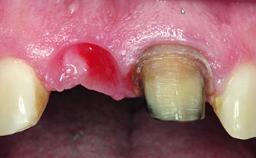

Replacement of a Failing Restored Upper Right Central Incisor, Ridge Preservation and Early Placement of an RC Bone Level Implant

A 23-year-old female, healthy and non-smoking patient had had tooth 11 temporarily restored following a trauma in adolescence. As the patient’s growth had since come to an end and the crown had fractured, she requested an implant-supported restoration of tooth 11. Moreover, the contralateral tooth 21 presented an old composite restoration at the mesial incisal edge. The periodontal tissues were healthy with periodontal probing depth values below 3 mm, but some inflammation was observed around the semi-submerged root of tooth 11.

Bone Volume Deficient horizontally, allowing simultaneous augumentation